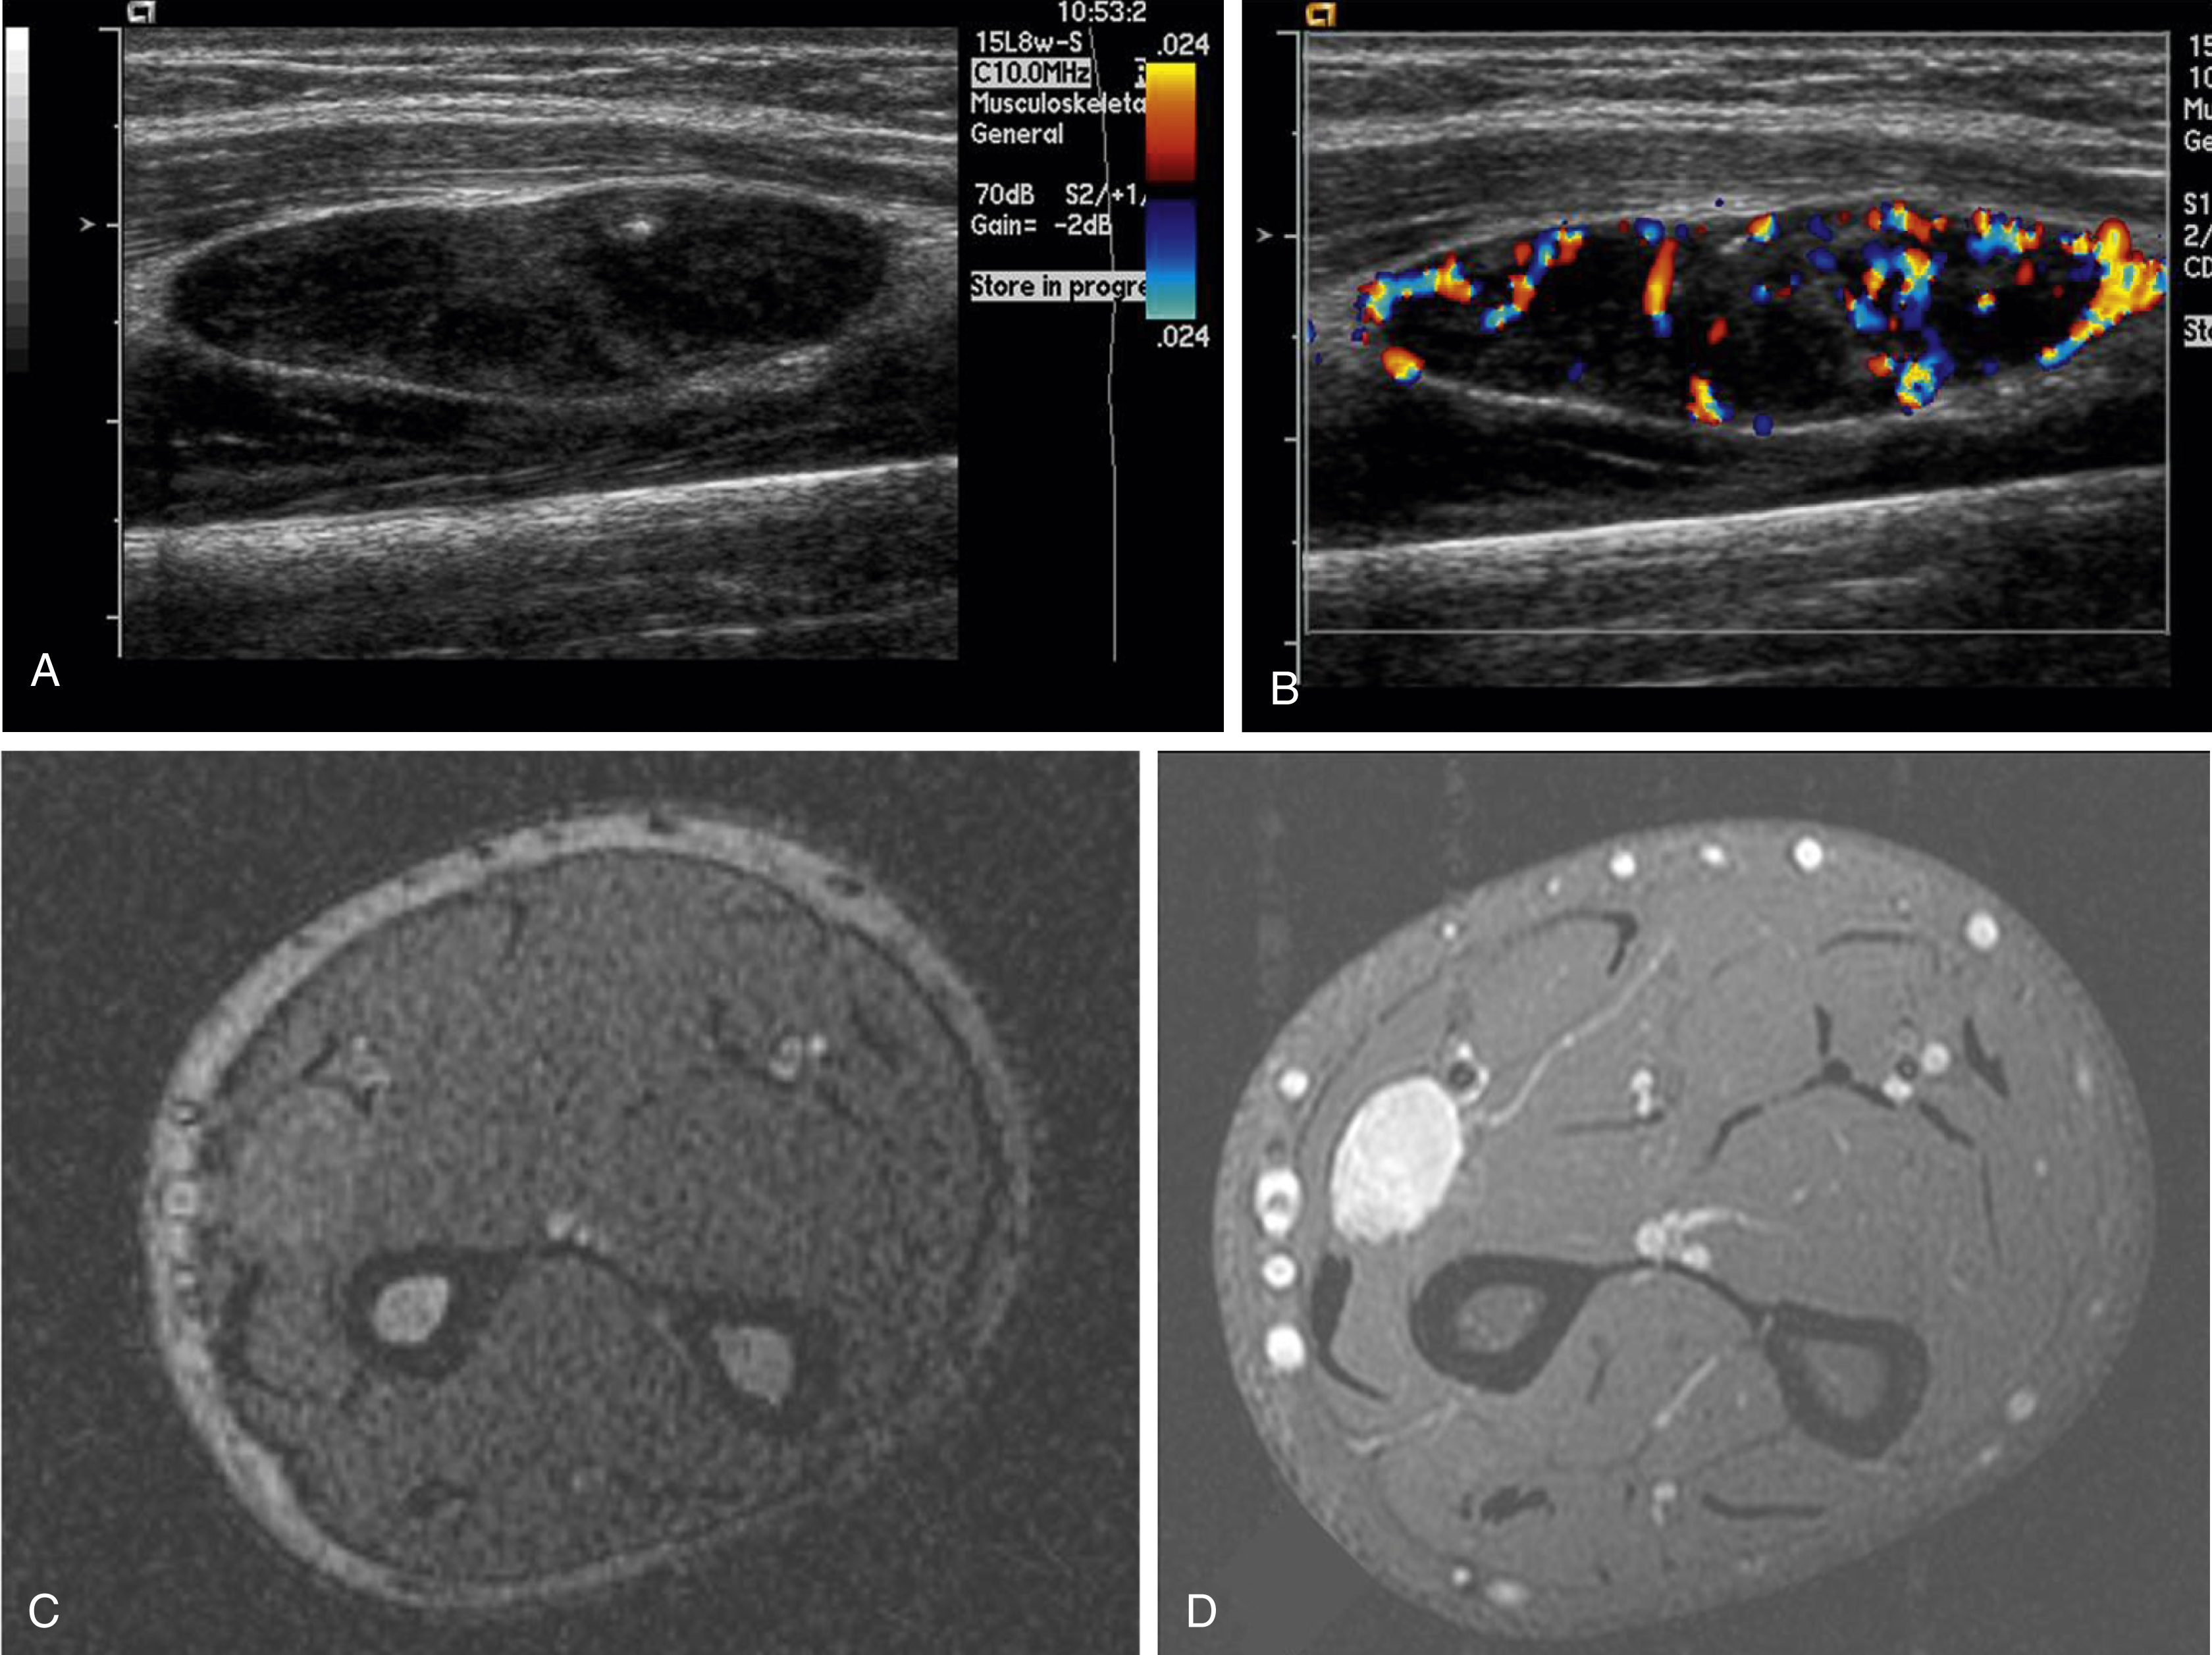

The majority of cases of synovial sarcoma occur in a juxtaarticular location, close to the joint capsule, tendons, and bursa. Only a minority of cases are intraarticular. Plain films findings may include a soft tissue density and spiculated calcifications, seen in up to 30% of cases. With US, synovial sarcoma can appear as a well-defined hypoechoic vascular mass near, but not within, the joint ( Fig. 16.4 ).

Fig. 16.4, Sixteen-year-old with growing left forearm intramuscular mass who on ultrasound has a well-circumscribed hypoechoic mass (A), which is hypervascular on color Doppler imaging (B) and axial gradient echo sequence demonstrates isointense signal to muscle (C) and postgadolinium T1-weighted fat-saturated sequence demonstrates homogeneous enhancement (D). Biopsy showed synovial sarcoma.

A classic MRI description of synovial sarcoma based on the most common findings is a juxtaarticular mass with a heterogeneous or triple-signal pattern (high-, intermediate-, and low-intensity areas) on T2-weighted imaging with fluid–fluid levels secondary to intralesional hemorrhage. Synovial sarcoma tends to be a well-defined mass isointense to muscle on T1-weighted images. Smaller lesions are homogenous, sometimes simulating cysts on unenhanced images. These small lesions, because of their homogenous hyperintense appearance on T2-weighted imaging and their propensity to displace, rather than infiltrate, adjacent structures, have been misdiagnosed as benign entities. Gadolinium is important in the evaluation of these masses. Unlike a cyst, these lesions will enhance.